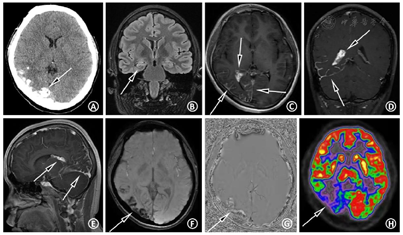

头计算机断层显像(computed tomography,CT)平扫:右侧颅腔、大脑半球较对侧略小,右侧枕颞叶多发斑片状钙化(图4A)。海马常规MRI:右侧海马硬化(图4B)。头颅磁共振静脉血管成像(magnetic resonance venography,MRV):未见明显异常。头增强MRI+SWI:右侧大脑半球体积小,CE-T1序列示右侧颞顶枕叶柔脑膜强化,右侧脉络丛较左侧增大、强化(图4C,图4D,图4E),SWI序列示右侧枕颞叶多发不均匀低信号影,相位图上呈高信号,符合钙化特点(图4F,图4G)。头正电子发射断层显像(positron emission tomography,PET)/CT:右侧颞顶枕叶体积小,脑实质萎缩,代谢减低或缺损,考虑致痫灶定位于右侧半球(图4H)。值得注意的是,CE-T1序列所示右侧颞极(图5A箭头)及左侧额叶高信号(图5C箭头)是否为异常柔脑膜强化不肯定,然而头CE-FLAIR序列可清晰显示右侧颞极存在柔脑膜强化(图5D),并除外左侧额叶的柔脑膜受累(图5F),提示患者的脑膜受累范围为单侧颞顶枕叶广泛受累。结合CE-T1、CE-FLAIR,以及SWI序列(未展示该层面SWI图像),考虑左侧额叶高信号(图5C箭头)为发育性静脉畸形可能。眼科视野检查示双眼左侧视野缺损。皮肤科会诊考虑右侧面部鲜红斑痣临床诊断明确,符合SWS皮肤表现。